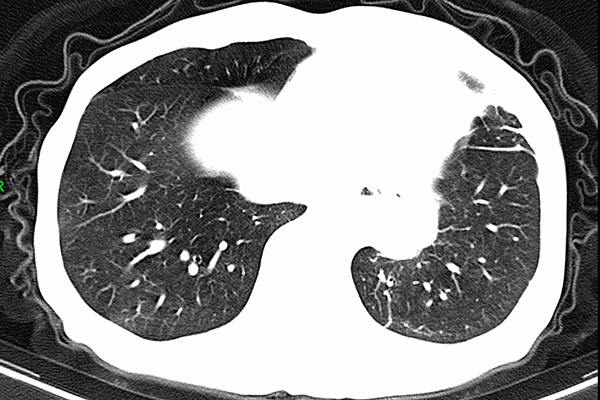

小编想告诉大家,千万不要慌!深呼吸!!只是疑似,淡定淡定!!!在我们得到初步的影像学检查后,最重要的是进行病理的确诊。肿瘤科流传一句话:“世界上最幸福的事情就是,你的肿瘤是良性的!”这个良性的结果就需要病理科医生来告诉我们。

所谓病理,也就是疾病发生的原因、发病原理和疾病过程中发生的细胞、组织和器官的结构、功能和代谢方面的改变及其规律。病理检查的意义可以用两个方面概括:①对于疾病的明确诊断,就是明确“疾病是什么”;②直接关系到对治疗方案的选择以及对病情预后的判断,也就是“该怎么办”。

在由多学科组成的临床病例讨论会中,通常由病理医生在会诊讨论的最后,公布病理诊断结果,一锤定音,揭开疾病表现的谜底。因此,医学界认为“最后一句决定生死的话,一定是要由病理医生来说的。”病理诊断又称“最后诊断”,病理医生被称为“医生的医生”。